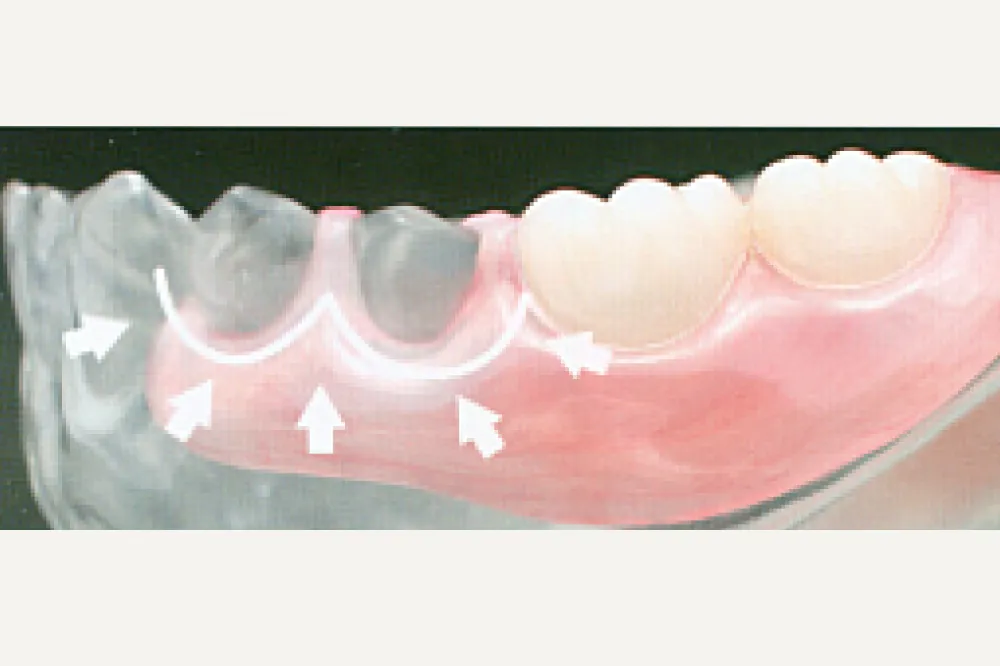

しっかりホールド。とても薄く、軽い。

歯茎から包み込む形状で、しっかり安定。さらに、丈夫でしなやかだから今までの入れ歯よりもかなり薄い入れ歯です。しかも超軽量。

しなやかフィット!

しなやかさが、お口の中で安定を守ります。